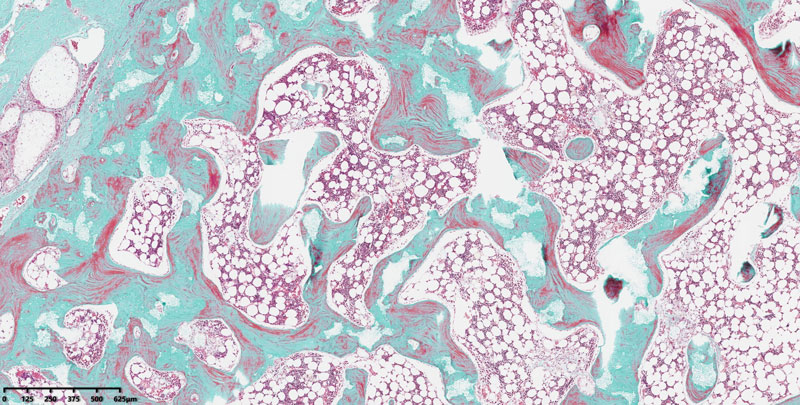

由英领医学团队自主研发的多孔β-TCP人工骨,具备精确调控的多级孔结构:总孔隙率稳定在70%(±10%),开孔孔隙率高达60%(±10%)。该材料不仅结构精密、力学性能优异,更以“轻透微构”的形态特征,高度模拟天然骨基质的微环境。

目前在动物实验中,该材料展现出显著的成骨性能——新生骨组织快速长入孔隙内部,与材料整合良好,实现了高效骨缺损修复。这一卓越成骨能力,源于其高度连通的多孔结构,既为细胞迁移和血管长入提供了三维空间,又为营养交换与代谢创造了理想条件。